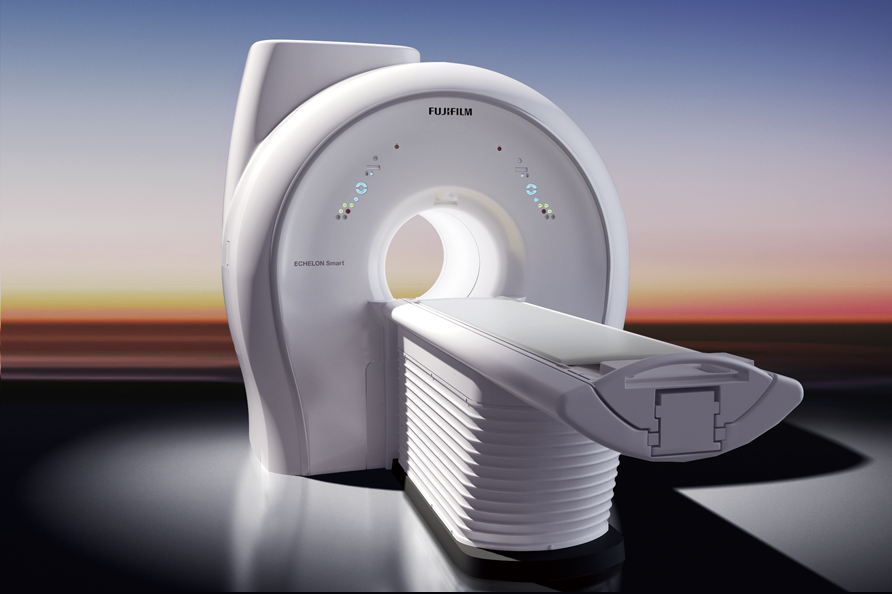

FUJIFILM ECHELON Smart 1.5T

FUJIFILM ECHELON Smart 1.5T